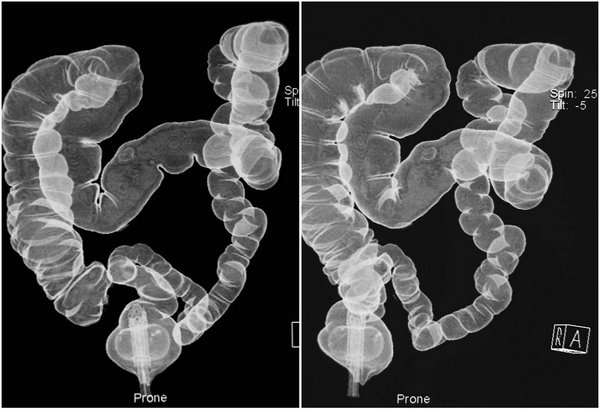

结肠CT充气造影技术:为大肠疾病提供了一种新的无创检查方法。结肠CT即利用CT采集结肠原始数据,在工作站使用计算机对其进行后处理,重建形成2D、3D图像,从而发现和诊断结肠病变。结肠CT成像已被证明与结肠镜检查的敏感性和特征性相当,被普遍作为一种预防、筛选结肠癌的经济有效的检查。

SSD(Surface Shaded Display,表面阴影显示)

VRT(Volume Rendering Technology,容积再现技术)